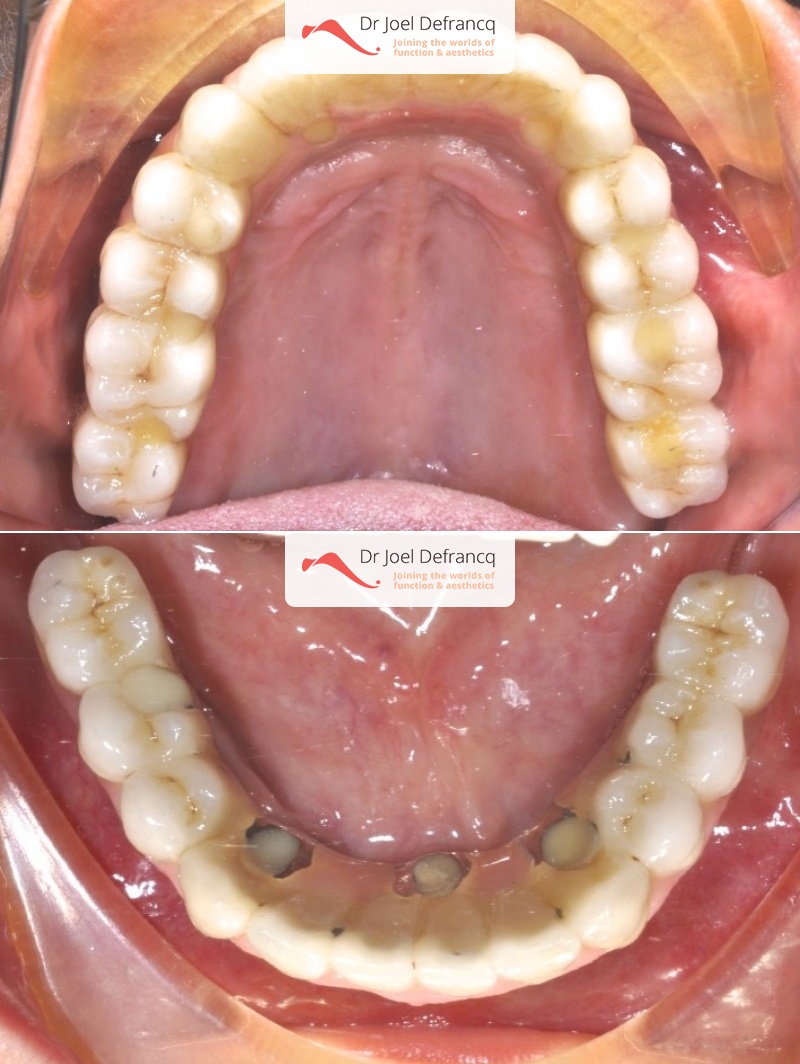

Daphne: from extreme atrophic to fixed teeth on implants

Behandeling tandheelkundige implantaten

- Vaste tanden op implantaten (bovenkaak)

- Vaste tanden op implantaten (onderkaak)

- Implantaten met beenopbouw